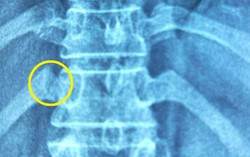

TAG thoát vị đĩa đệm

4 thói quen "tra tấn" đĩa đệm cột sống thắt lưng mỗi ngày, cột sống khỏe mấy cũng sớm "hỏng"

Phòng & chữa bệnh 11:53 15/05/2025Bệnh thoát vị đĩa đệm thắt lưng đang dần trẻ hóa, nhất là với dân văn phòng.